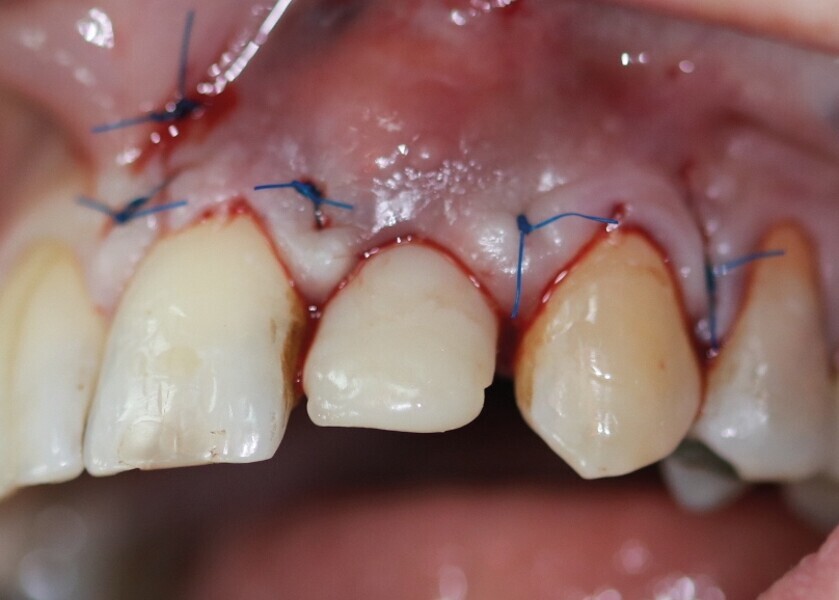

Pour connaître la profondeur de trépanation, il suffit d’enfoncer la sonde parodontale et de mesurer l’épaisseur de gencive sur l’os. En y ajoutant 4 mm, la profondeur finale est obtenue pour avoir suffisamment d’os. Une fois la carotte ostéogingivale prélevée (Figs. 23 et 24), il ne faut pas séparer l’os de la gencive, mais réduire l’épaisseur gingivale en supprimant la partie kératinisée (Fig. 25). Un implant cylindroconique (Straumann BLT 3,3 SLActive Roxolid) est parfaitement ancré (Fig. 26). La carotte d’os et sa gencive toujours adhérente, sont alors impactées transversalement à l’implant (Fig. 27). La partie osseuse spongieuse est au contact de l’implant, pendant que le conjonctif qui y est attaché, est utilisé comme un greffon conjonctif enfoui sous le lambeau vestibulaire.

Cette technique devient alors une combinaison entre la greffe osseuse simultanée à l’implant, décrite dans le premier cas clinique, et une greffe gingivale (Figs. 28 et 29). Lorsque la stabilité primaire est importante, la mise en esthétique peut être envisagée. Ce sont les implants cylindroconiques qui donneront le meilleur ancrage. Des points de suture matelassiers verticaux plaquent et repositionnent verticalement les papilles interdentaires (Monofilament Seralon 5.0).

Une dent provisoire transvissée est confectionnée sur un pilier PMMA par couches successives de composite (Fig. 30). La couronne définitive céramo-zircone sur pilier variobase est transvissée à quatre mois. Un contrôle à deux ans montre une stabilité de l’environnement parodontal (Fig. 31).